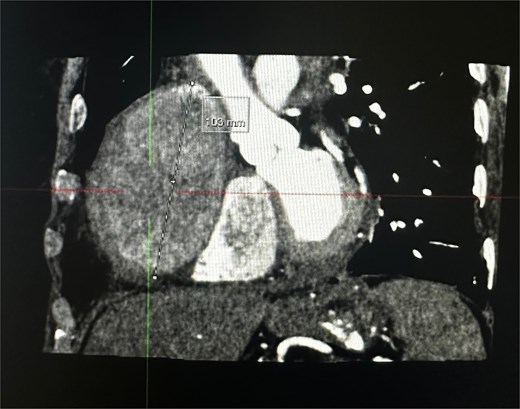

An 82-year-old female presented to the emergency department complaining of progressive severe central chest that was pleuritic in nature, radiating to her right arm. Following a bedside echo, the patient underwent coronary angiography, where a giant right CAA was diagnosed (Fig. 1). Subsequent, contrast computed tomography (CT) scan further characterized the aneurysm, and highlighted significant compression was uncovered compressing both the right atrium and ventricle (Fig. 2). The right coronary aneurysm was measured cross-sectional dimensions of 8.3 × 7.4 cm (Fig. 3) and 10 cm in length (Fig. 4). Following Heart Team discussion, the patient was scheduled for an aneurysmectomy and coronary artery bypass to repair the extensive disease.

Coronal plane of a contrast thorax CT scan showing the giant coronary aneurysm.